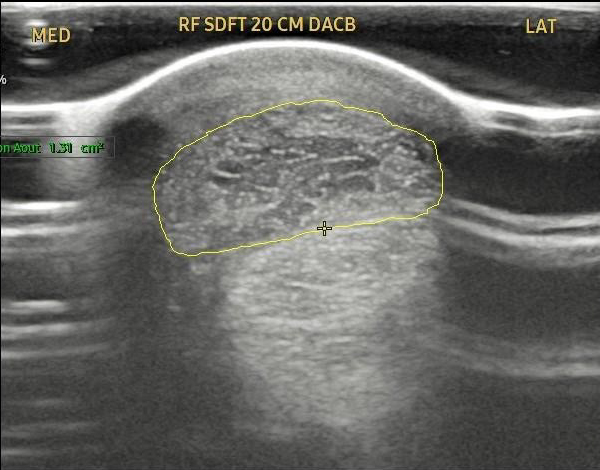

Case Study 2 – Equine Tendon Regeneration

The attached images show a pre- and post-treatment equine superficial digital flexor tendon injury.

This horse received two injections spaced one month apart and at the 2 ½ month point has produced a reduction in the core tendon lesion of approximately 70%.

Source: Temecula Creek Equine